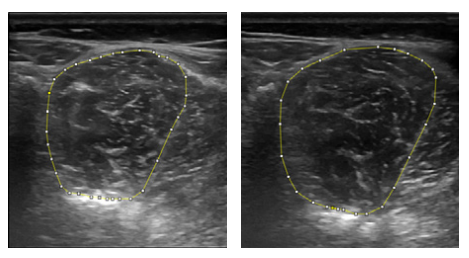

Abb.2: Segmental angeordnete autochthone Rückenmuskeln